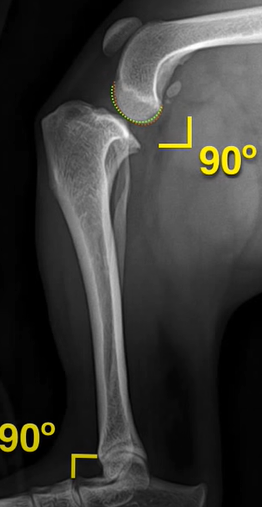

The Stifle and Tarsus must be 90°flexed;

Following the identification of points of interests, and drawing of the lines of interest, i.e. the Functional Tibial Line (FTL) and the Medial Tibial Plateau Line (MTPL), another line is drawn such that the relation of new line and the FTL is 90°. Tibial plateau angle is the angle between this new line and the MTPL; this is shown in Fig. 3.

Normal TPA values can range from 18 to 25 degrees [1]; the large range can be attributed to the large range of breed, body weight, age etc.